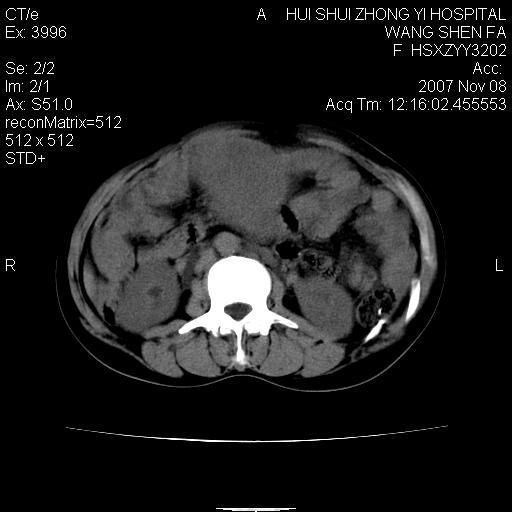

腹腔及盆腔内可见巨大软组织肿物影,内部密度欠均匀,边界尚清晰,周围组织受压移位明显,右侧输尿管受压明显,上端扩张肾盂轻度积水,病灶外形分叶明显,似多个肿物融合而成。考虑来源于间叶组织的恶性肿瘤可能性大

下腹部巨大软组织影,密度不均匀,并可见分隔,病灶边缘较清,肠管受压移位。子宫未显示。盆腔、双侧腹股沟未见明显肿大淋巴结。考虑:1.卵巢病变可能性大,囊腺癌>卵巢癌>囊腺瘤.2.多发性阔韧带子宫肌瘤待除外.

腹腔及盆腔内可见巨大软组织肿物影,内部密度欠均匀,边界尚清晰,周围组织受压移位明显,膀胱前上移位,右侧输尿管受压明显,上端扩张肾盂轻度积水。考虑:1卵巢病变可能性大,囊腺癌>卵巢癌>囊腺瘤.2 子宫病变,子宫肌瘤?

下腹部巨大软组织影,密度不均匀,并可见分隔,病灶边缘较清,肠管受压移位。病灶下部与子宫及附件关系密切。盆腔、双侧腹股沟未见明显肿大淋巴结。考虑:1.卵巢实质性肿瘤可能性大,卵巢癌>颗粒细胞>卵泡膜细胞瘤>纤维瘤.2.多发子宫肌瘤待除外.